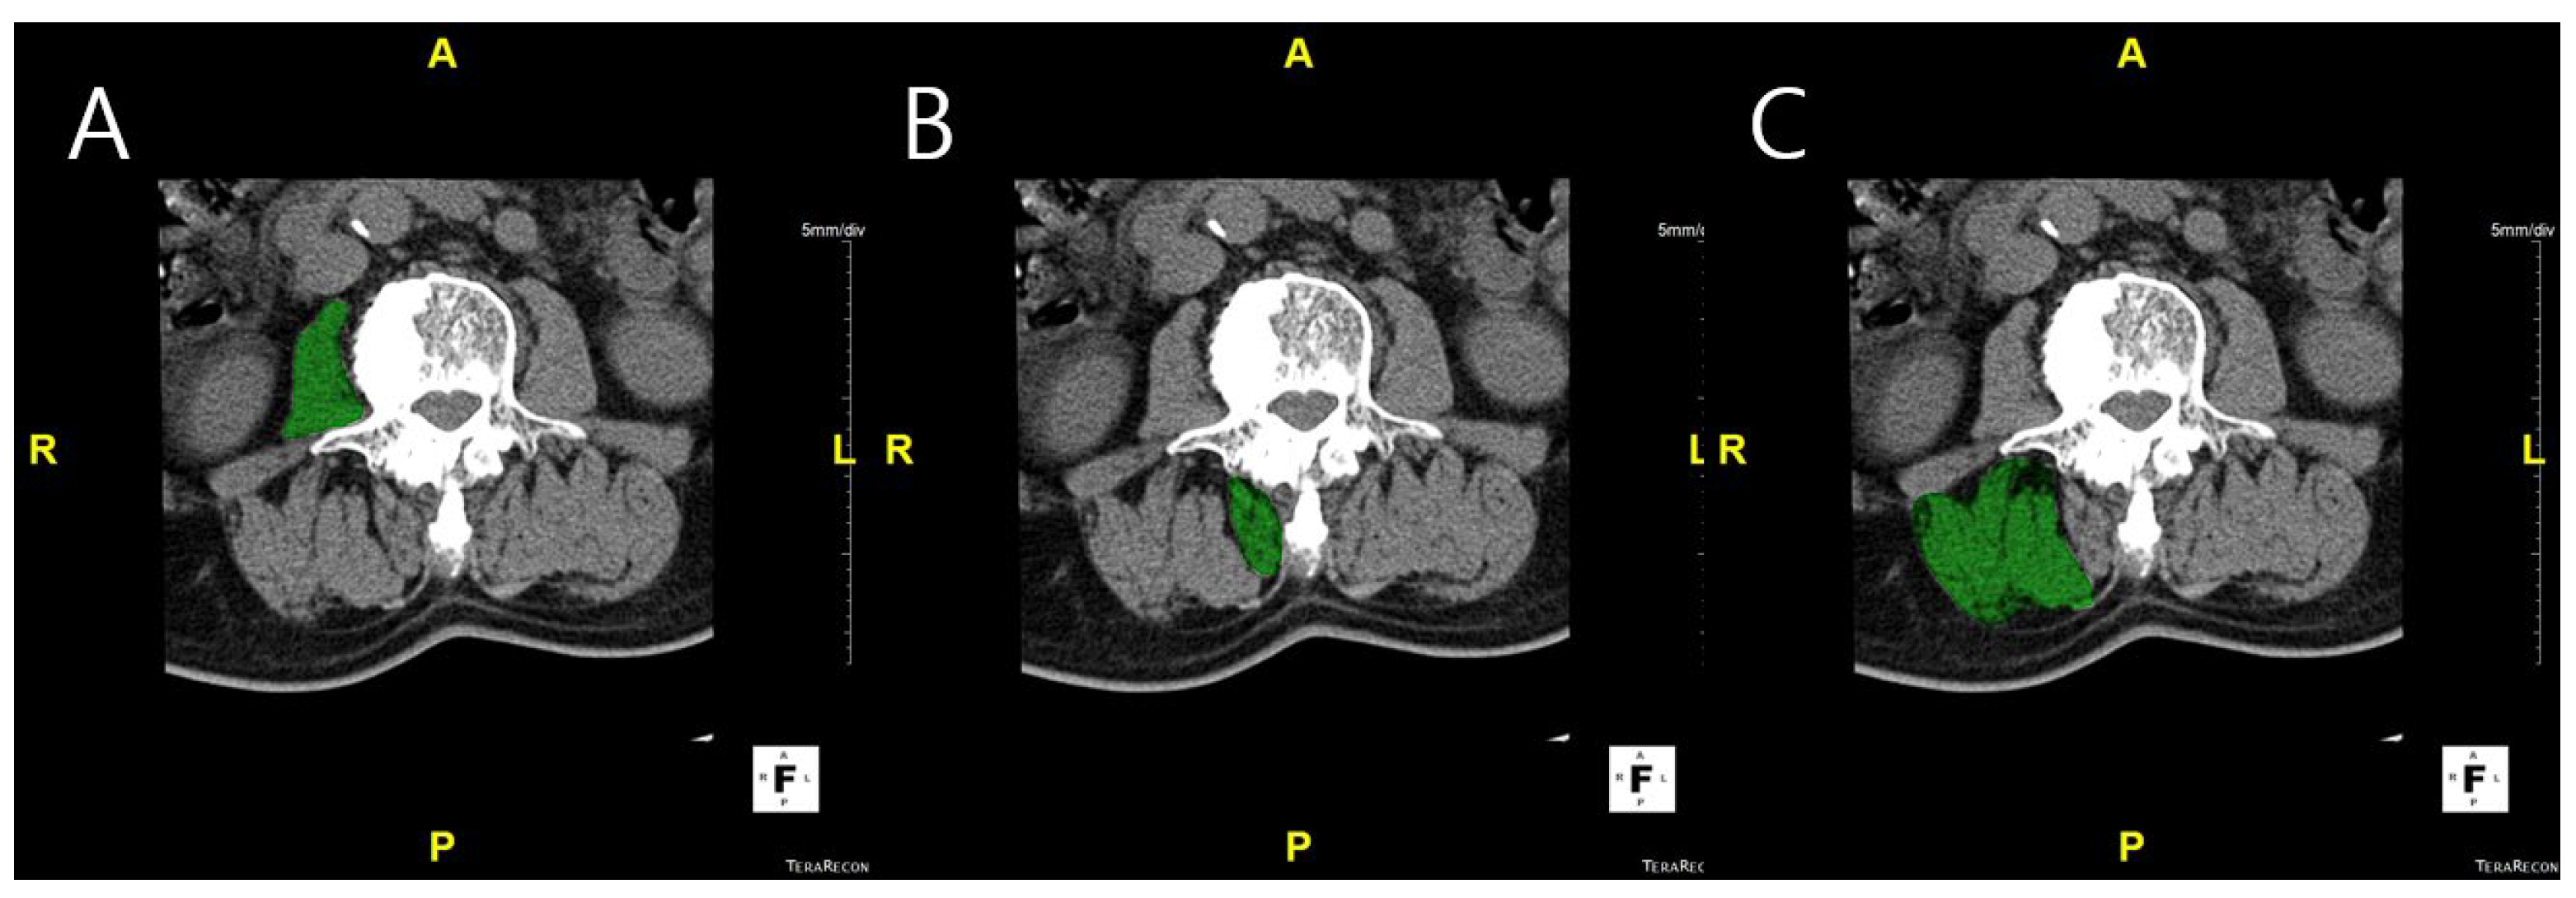

Measurement of muscle volume and fat infiltration ratio: MV was measured using CT scans. L-spine images were obtained from the upper endplate of T12 to the lower endplate of S1, using a 256-slice CT scanner (Somatom Drive, Siemens Healthineers, Erlangen, Germany). CT examinations were performed with 2 mm collimation and 120 kV. The DICOM images were imported into Aquarius iNtuition Viewer (TeraRecon Inc., Foster City, CA, USA). Regions of interest (ROIs) were manually delineated on each axial CT slice to measure the muscle volume and fat infiltration. ROIs were drawn to include the entire cross-sectional area of the psoas, multifidus, and erector spinae muscles, carefully following the visible muscle boundary while excluding adjacent fat, bone, and other non-muscular tissues. Muscle volume was calculated by summing the cross-sectional areas of the ROIs across slices, and fat infiltration was determined based on the Hounsfield unit distribution within each ROI (Figure 1). Fat infiltration was calculated by analyzing the attenuation of muscle tissue on CT images. Skeletal muscle was defined using a Hounsfield unit (HU) range from −29 to +150, which has been widely applied in both cadaveric validation studies and clinical research [8,9,10,11]. This range differentiates skeletal muscle from adipose tissue (−190 to −30 HU) and has been used across diverse populations, including elderly cohorts and patients with spinal disorders, supporting its applicability to our study cohort. Nevertheless, we acknowledge that population-specific HU thresholds may provide additional accuracy, and future studies could explore tailored HU cut-offs for ADS patients. The proportion of muscle tissue within this HU range was then calculated as a percentage of the total muscle volume, providing the degree of FI [12].

Figure 1. Axial CT images showing ROI of paraspinal muscles using Aquarius iNtuition Viewer (TeraRecon Inc., Foster City, CA, USA). The muscles highlighted in green indicate the segmented ROI. (A) Psoas muscle. (B) Multifidus muscle. (C) Erector spinae muscle.